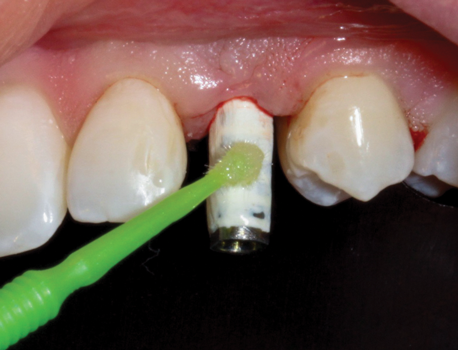

(38.) The opaqued titanium provisional abutment was gently tightened onto the implant.

Figure 38

(39.) The composite tooth shell was modified to fit around the abutment, positioned intraorally, and bonded to the abutment with flowable composite in the incisal half.

Figure 39

(40.) Following removal of the partially completed provisional restoration from the mouth, the emergence area is filled in with flowable composite and refined to create a narrow S-curve emergence profile.